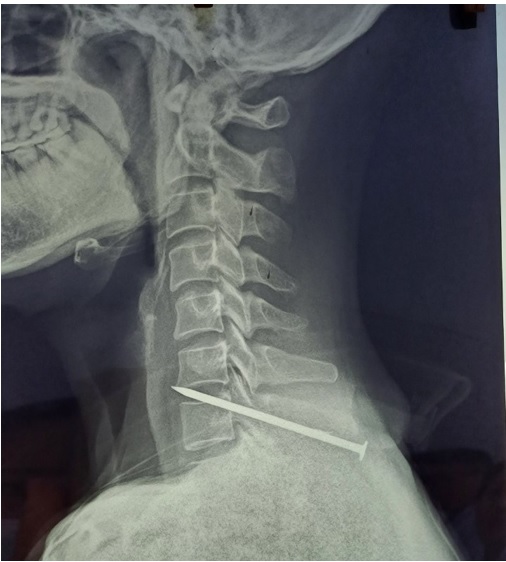

Bệnh nhân nam N.V.K, 51 tuổi, địa chỉ ở Bắc Giang. Theo người nhà bệnh nhân, khoảng 15h ngày 14/11/2023, bệnh nhân đang làm việc tại khu công nghiệp thì không may bị chiếc đinh xuyên vào vùng sau vai từ súng bắn đinh. Ngay sau đó, bệnh nhân được các đồng nghiệp đưa vào Trung tâm y tế thành phố Từ sơn cấp cứu. Sau khi được khám, sơ cứu vết thương, chụp cắt lớp vi tính phát hiện hình ảnh dị vật xuyên qua cột sống vùng cổ nối tiếp ngực tương ứng đốt sống cổ C7 và được chẩn đoán vết thương hở của cổ - vết thương xuyên thấu vùng cổ. Bệnh nhân nhanh chóng được chuyển đến Bệnh viện Đa khoa tỉnh vào lúc 16h trong tình trạng: bệnh nhân tỉnh, các chỉ số sinh tồn ổn định, vùng cạnh sống sau vai trái có dị vật kim loại làm lõm vùng da chỗ lỗ vào, rỉ máu, vận động vùng cổ hạn chế nhiều do đau, không có dấu hiệu liệt.

Hình ảnh chụp CLVT của bệnh nhân tại TTYT Từ sơn